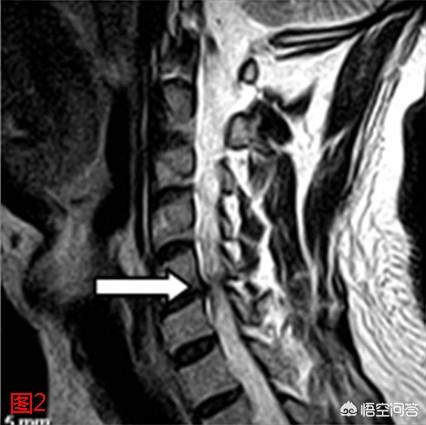

5. hernie discale cervicale

Comme indiqué dans la question, les hernies discales dans le segment cervical inférieur peuvent comprimer les nerfs et entraîner l'apparition d'un engourdissement des mains, mais elles sont souvent accompagnées d'une gêne au niveau du cou et ne doivent pas être diagnostiquées en voyant une hernie sur un rapport d'imagerie ; le piégeage du nerf du plexus cervical peut également entraîner des symptômes au niveau des membres supérieurs.

La hernie discale cervicale est généralement diagnostiquée à l'aide d'un film, mais je vous enseigne une technique de diagnostic qui consiste à appuyer sur l'expérience du cou, vous vous asseyez droit sur la chaise, laissez les mains d'une autre personne sur le dessus de votre tête, appliquez lentement une pression, si l'engourdissement de la main aggrave les symptômes, on peut diagnostiquer une hernie discale cervicale ! La période aiguë de la hernie discale cervicale est principalement calme, trois ou quatre jours après la période de récupération peuvent être le conditionnement tui na plus le conditionnement sanguin par moxibustion, la traction auxiliaire !

Au sens propre, c'est la colonne cervicale qui appuie sur les nerfs, et non les disques qui appuient sur les nerfs ou sur les nerfs de la moelle épinière. En effet, ce n'est que lorsque la cause est claire que le type de spondylose cervicale peut être identifié avec plus de précision et que les options de traitement peuvent être choisies.

La spondylose cervicale radiculaire est causée par une hernie ou un prolapsus du nucleus pulposus, des ostéophytes ou une arthrite traumatique des facettes postérieures, la formation d'éperons osseux dans les articulations à crochets et le relâchement et le déplacement des trois articulations adjacentes (articulations intervertébrales, articulations à crochets et facettes postérieures), qui peuvent tous provoquer une irritation et une compression des racines nerveuses de la colonne vertébrale, entraînant des douleurs musculaires ou un engourdissement des doigts de la tête, du cou, des épaules et même des bras.

L'autre type est la spondylose cervicale de la moelle épinière, également connue sous le nom de spondylose cervicale paralysante. Elle est due à la dégénérescence des articulations intervertébrales cervicales, telle qu'une hernie discale, des éperons osseux sur le bord postérieur du corps vertébral, une hyperplasie de l'articulation vertébrale crochue, une ossification du ligament longitudinal postérieur, une hypertrophie ou une calcification du ligamentum flavum, ce qui entraîne une compression de la moelle épinière dans le canal vertébral ou une ischémie de la moelle épinière, puis un dysfonctionnement de la moelle épinière ; la spondylose cervicale de la moelle épinière est donc l'un des troubles de la compression de la moelle épinière, qui peut entraîner une invalidité grave, représentant 10 à 15 % de l'ensemble des spondyloses cervicales. Pour ce type de spondylose cervicale, la chirurgie est indispensable, et toutes les méthodes non chirurgicales ne peuvent qu'atténuer les symptômes ou ralentir l'évolution de la maladie.

L'engourdissement des mains est dû à la compression des racines nerveuses correspondantes en raison de la prolifération des articulations et des ligaments de la colonne cervicale ou de la hernie des disques intervertébraux.